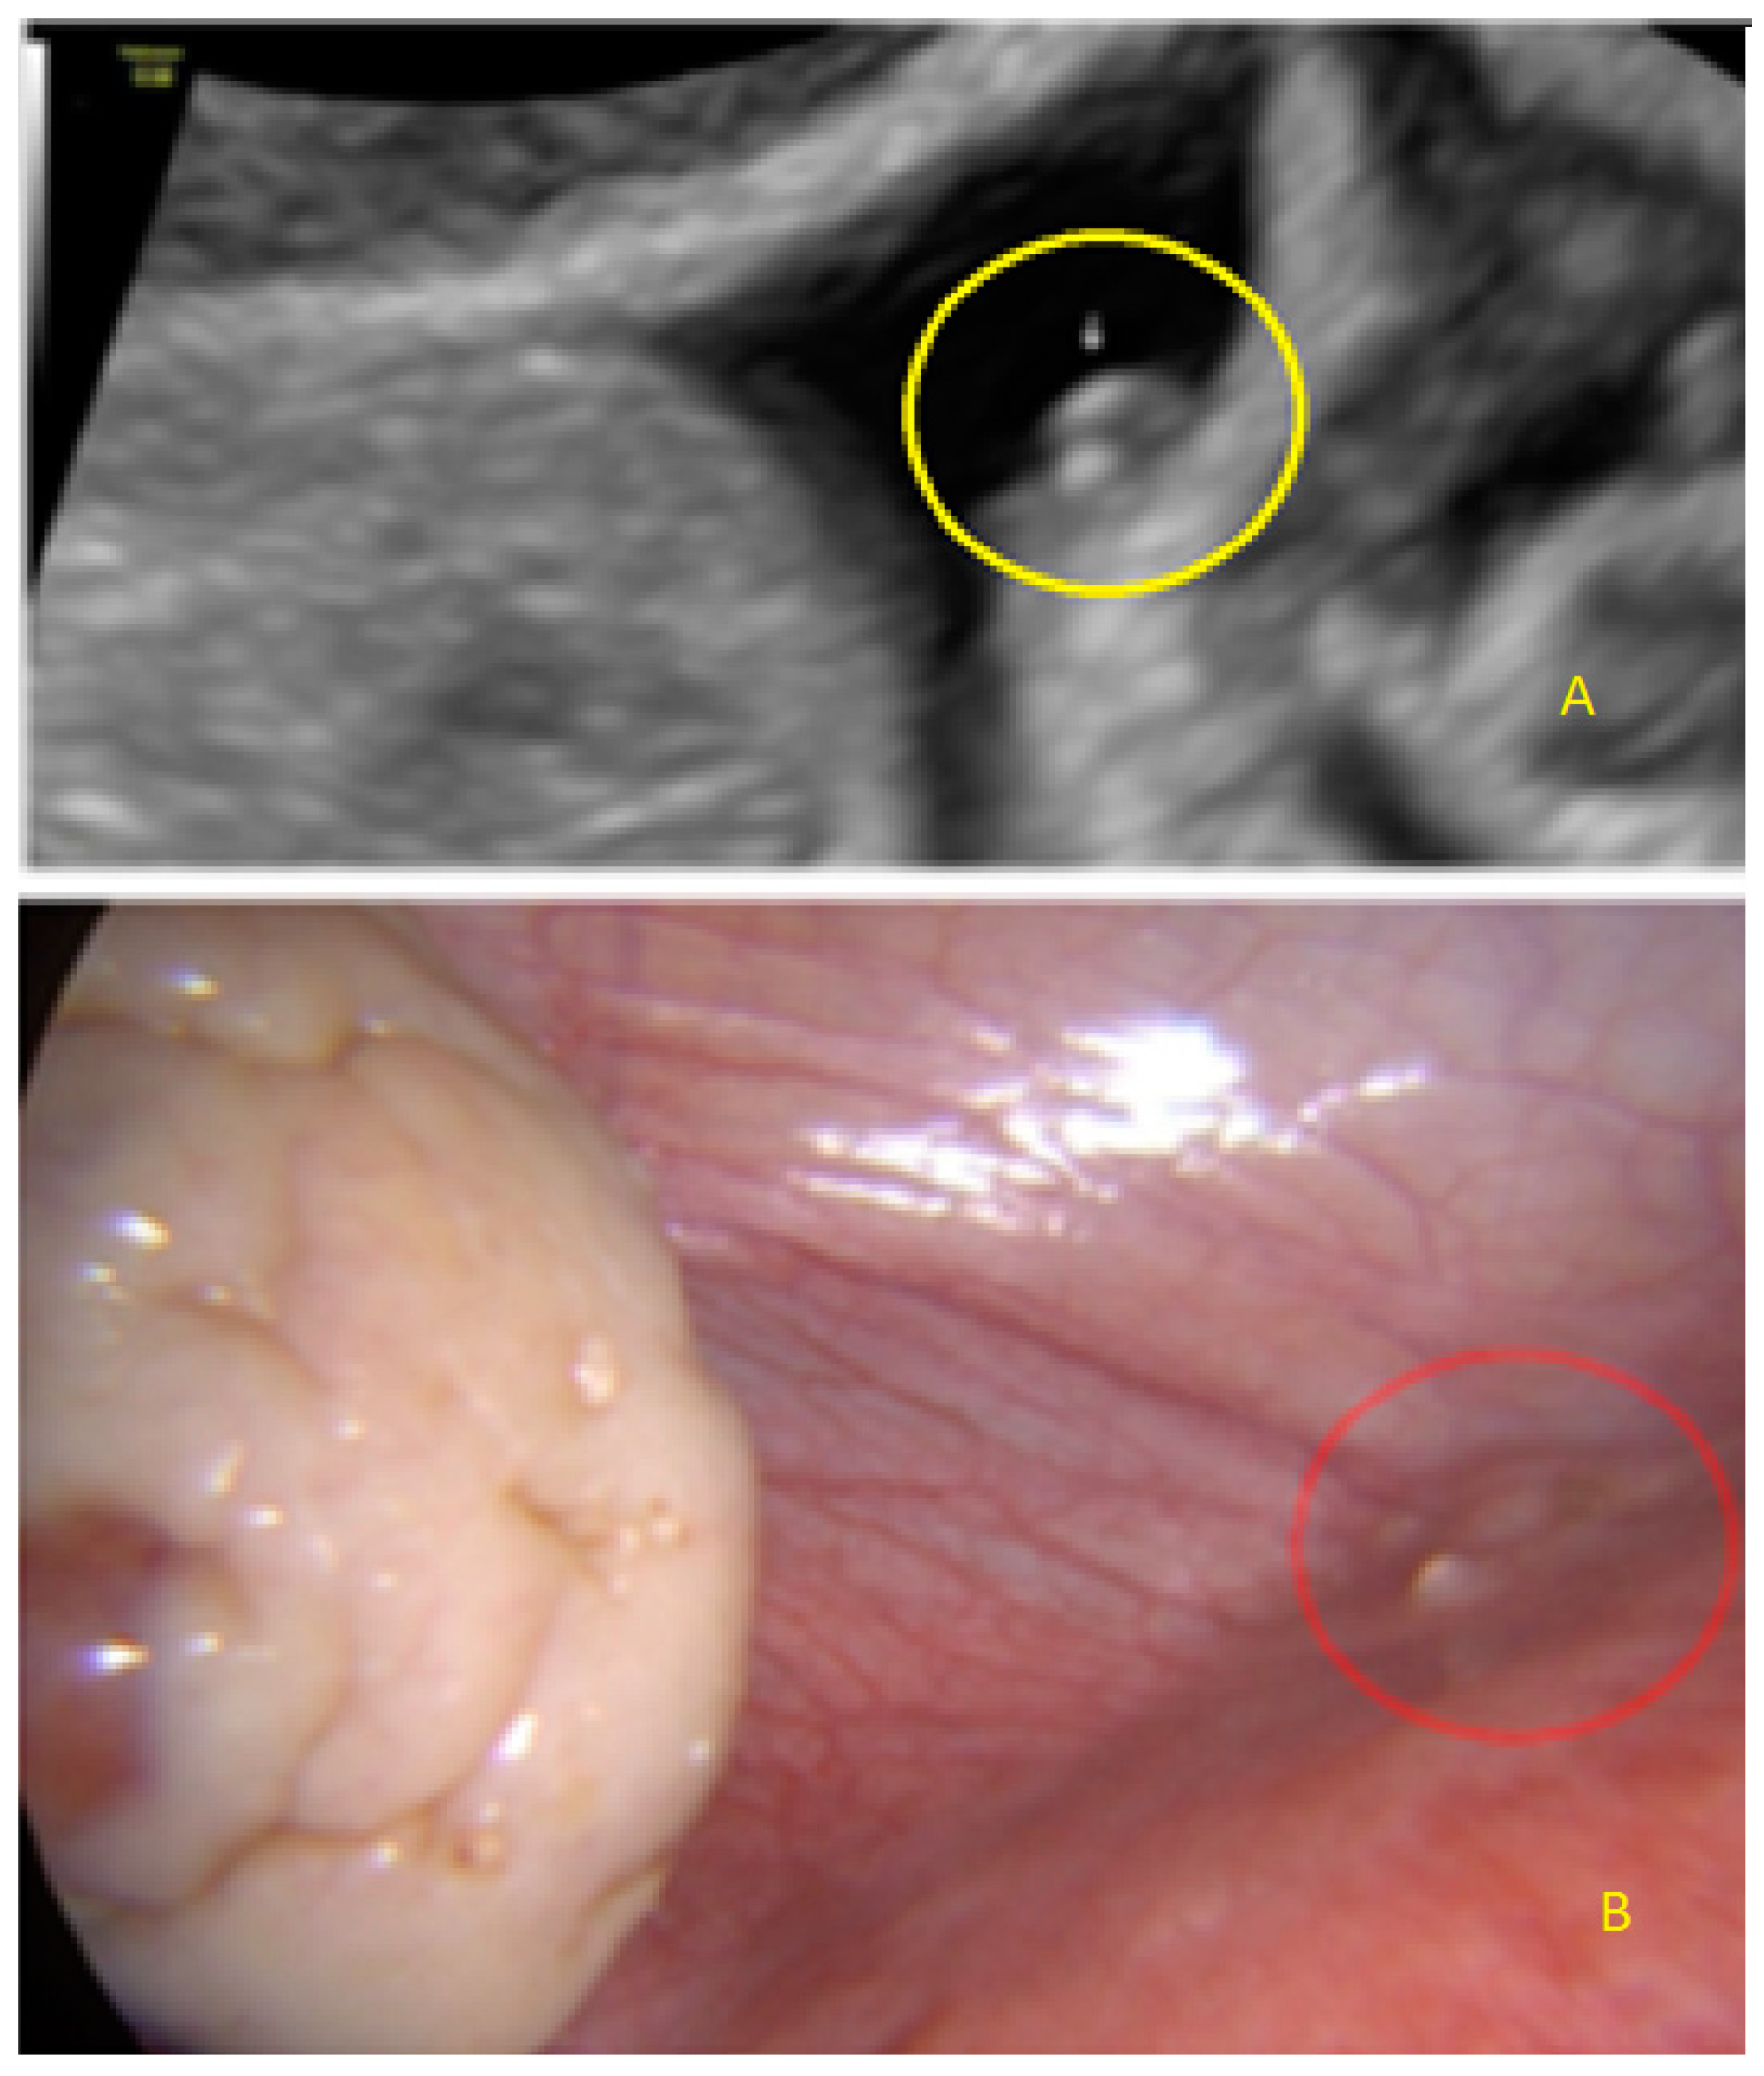

- The lesion may be convex, protruding from the peritoneal surface into the peritoneal cavity (we called this “bulging”), or it may appear as a concave defect in the peritoneum (we called this a “pocket”).

- The presence of hyperechoic foci (we called this a “pearl”).

3.1. Cystic Solitary Lesion